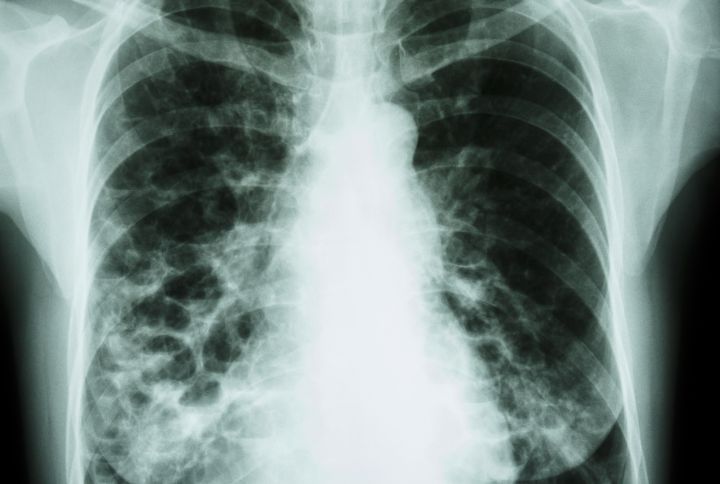

La dilatation des bronches (DDB) ou bronchiectasie ou bronchectasie est une pathologie pulmonaire. Souvent sans cause connue, ou à la suite d'une infection, une partie des bronches est dilatée causant toux chronique, douleur, expectoration de mucus, gêne respiratoire. Le diagnostic de la bronchiectasie nécessite une évaluation approfondie comprenant des tests d'imagerie et des examens fonctionnels respiratoires.

La bronchectasie, ou dilatation des bronches, peut être localisée, c’est-à-dire n’affecter qu’une région d’un seul poumon, ou elle peut être diffuse et donc toucher plusieurs régions des deux poumons.

Pour identifier la cause d’une bronchectasie, plusieurs examens sont nécessaires. Ils englobent une analyse de sang à la recherche d’un agent infectieux, une bronchoscopie (examen de référence pour la visualisation de la trachée et des bronches), une radiographie du thorax, une tomodensitométrie, mais aussi exploration fonctionnelle respiratoire (EFR).